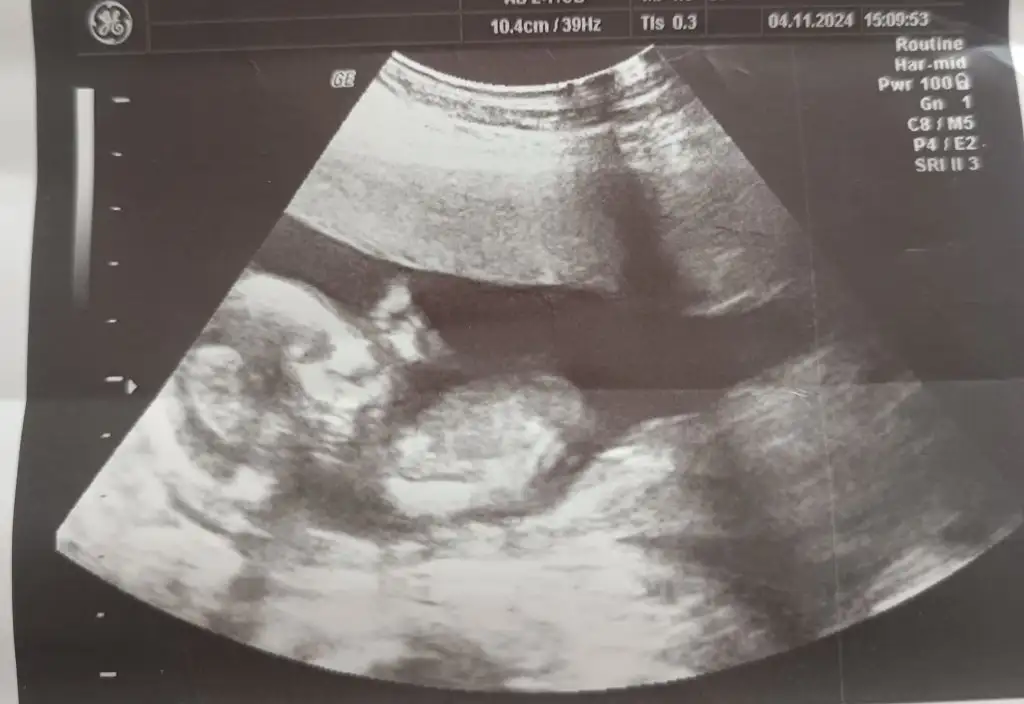

Merhaba benimkini de söyler misiniz? Karından, 14+4 haftalık

• IMG-20241226-WA0010.webp

IMG-20241226-WA0010.webp

25,4 KB · Görüntüleme: 79